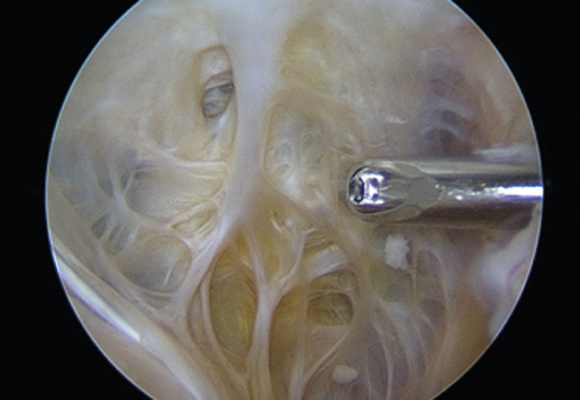

낭종 크기가 크고 통증이 심한 경우 무릎 뒤쪽의 혹을 제거하는 수술 시행

ㆍ환자 동의를 받은 자료이며, 이미지 사진은 실물과 다를 수 있습니다. (20.12.03)